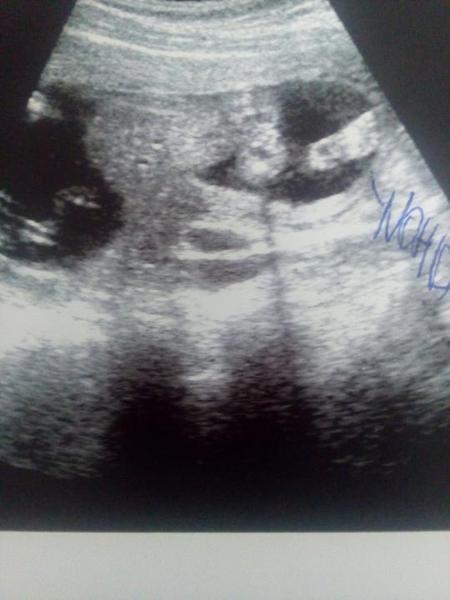

@zuzkabrhelova já bych řekla holčičku?

@zuzkabrhelova holčička,vidím 3čárky 😉

@zuzkabrhelova holka🙂

@zuzkabrhelova koukam,ze je to jakoby zespodu plavajici miminko-nalevo bricho,ze? Pindik tedy visi dolu a neni videt 🙂 mas i dukaznou s pindikm? Presne na takovve fotce nam u druheho syna rekli v 16tt,ze je to holka a tak to v 21tt bylo velkym prekvapenim🙂

Jj je hlavou dolu takže pin dík tam někde visí 🙂 nene pindika jsme nevideli. @estrellita